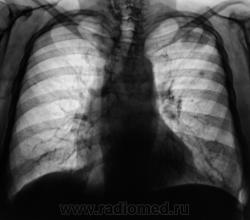

А, на верхушке, тихо "улыбалась" фокусная тень.

Жалоб нет. Ваше мнение уважаемые коллеги?

Прослеживается связь с корнем, плевра утолщена, рядом очаговая тень(отсев?), скоре всего туеркулез.

А, если туберкулёз, то, по всей видимости, инфильтративный?

Да, возможно даже каверна сформируется, фокус достаточно крупный, неоднородной структуры.

учитывая отсутствие клиники, наличие неоднородной фокусной тени, отсев? на первый  план в диф. ряд можно выставить туберкулез, сделать Т-грамму левой верхушки, и пусть терапевты проведут минимальные обследования...

Слева в S2 похоже на туберкулому (очерченные контуры в отличии от инфильтрата).

Коллеги!!! Спокойный окружающий фон, отсутствие четкого контура, мелкая лучистость по периферии образования, лимфангит к корню, подходящая интенсивность. По-моему здесь классический периферический рак.

Во- первых:я бы сказал, что окружающий фон не совсем спокойный, т.к. за III ребром очаг.Во-вторых периферический рак лёгого (бронха), как правило растёт вдоль длинника бронха- мы этого в данном случае, не видим. В-третьих: при туберкулёзе, то же бывает "дорожка" к корню. Так, что говорить о классическом периферическом раке легкого не стоит.

Есть все основания для подозрений в сторону периферического рака...  Кроме того насторожила картина в нижней части правого корня - нет полоски Прозорова.

Итак, если, я правильно понял, то дифференциальную диагностику нужно проводить между периферическим раком легкого и туберкуломой?

Вообще-то дискуссия," что это периферический рак или туберкулома"- подтверждение старой истины:рентгенологически дифференцировать периферический рак и туберкулому практически невозможно.

Пациент прооперирован в областном онкологическом диспансере. Окончательный диагноз, включая всевозможную морфологию - туберкулома.